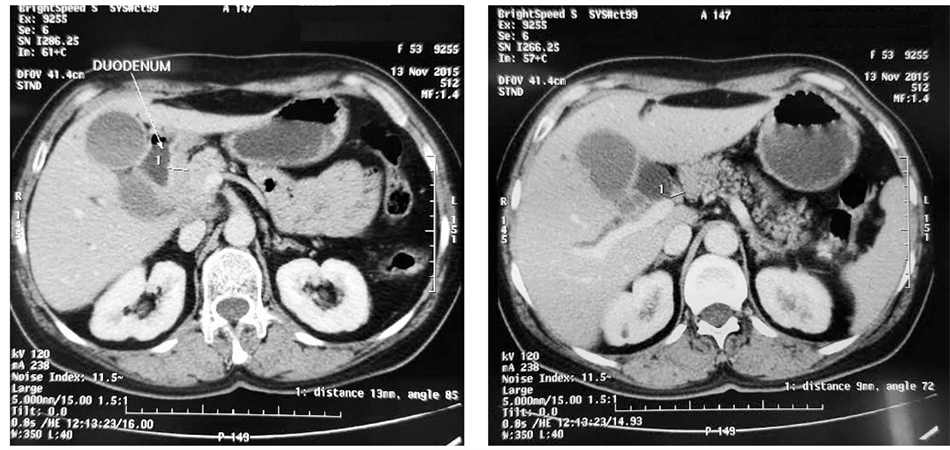

A duodenal prosthesis was introduced via an endoscopic retrograde cholangiopancreatography (ERCP) (Figure 2) but the procedure failed to catheterize the bile duct. An external draining of the bile was performed and biological parameters started to improve. Tumor markers, cancer antigen 19-9 (CA 19-9) and can- cer antigen 125 (CA 125) were high (121.3 ui/ml and 123.5 ui/ml). The histological analysis of a CT guided biopsy revealed that the tumor was an undifferentiated carcinoma (Figure 3).

Figure 2. Endoscopic image of an exophytic tumor of the duodenum (arrows).